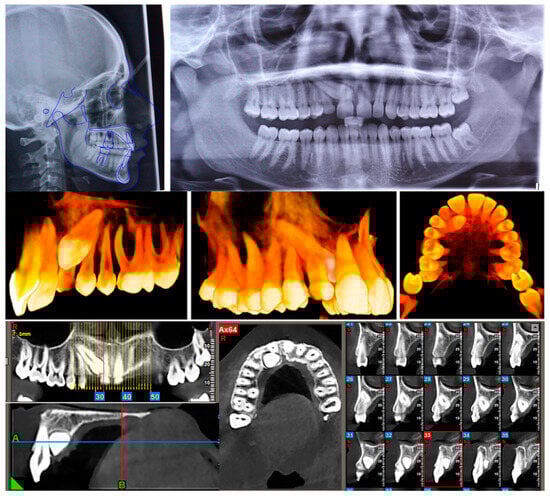

2.2. Clinical Findings

2.3. Diagnostic Assessment